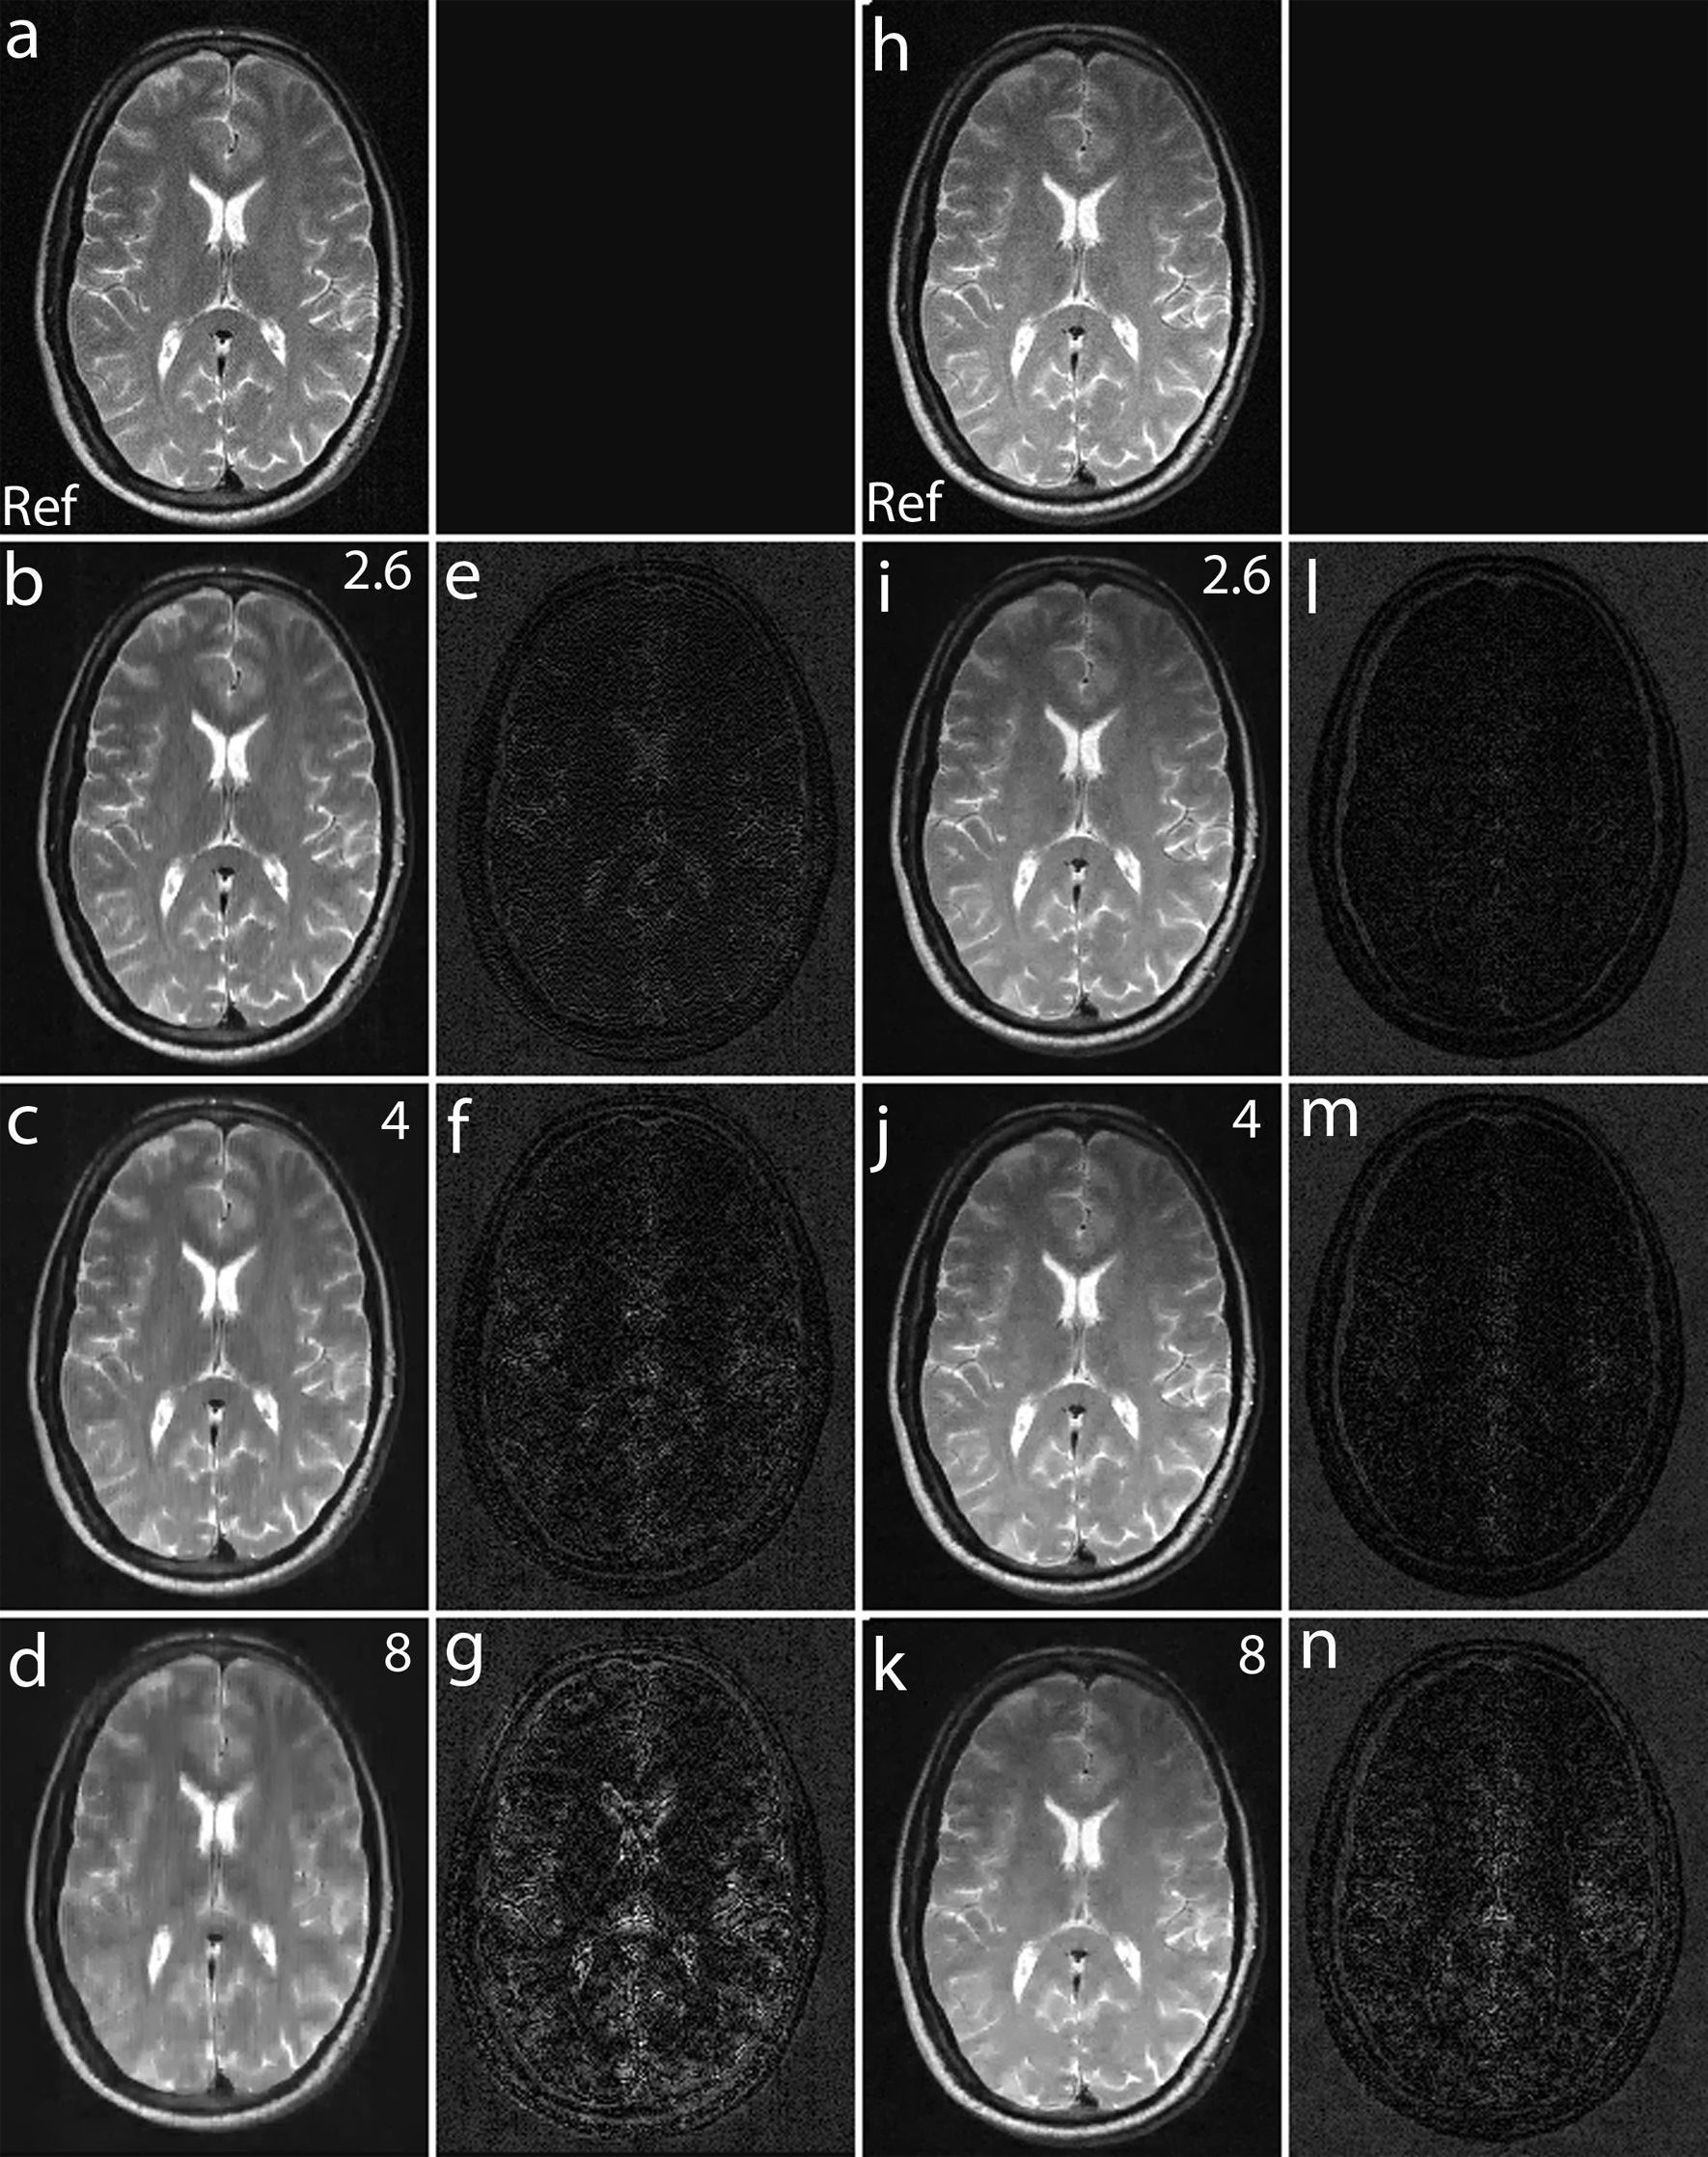

To validate the feasibility of the proposed reconstruction method, we performed retrospective under-sampling on the acquired noiselet encoded data and Fourier encoded data to simulate accelerated data acquisition. After retrospective under-sampling, the unconstrained optimization program (10) was solved using the non-linear conjugate gradient method to reconstruct the desired image for different acceleration factors. Fig. 12 (a)-(c) shows the reconstructed images for the acceleration factors of 4, 8 and 16 on the Fourier encoded data while Fig. 12 (d)-(f) shows the corresponding difference images. Similarly, Fig. 12 (g)-(i) shows the reconstructed images for the acceleration factors of 4, 8 and 16 on the noiselet encoded data, and Fig. 12 (j)-(l) shows the corresponding difference images for noiselet encoded MCS-MRI. These results on the acquired data are consistent with the simulation results and indicate that the noiselet encoding is superior to the Fourier encoding in preserving resolution.

Fig. 12 (A-H) shows the zoomed portion of the reconstructed images with Fourier encoding and noiselet encoding. One can distinguish between the small dots in the zoomed images reconstructed with noiselet encoding while it is difficult to distinguish these dots in the images reconstructed with Fourier encoding. This demonstrates that noiselet encoding is able to preserve resolution better than the Fourier encoding. Fig. 13 show the images reconstructed with Fourier encoding and noiselet encoding for various acceleration factors on the data acquired for one axial slice of the brain. Since the SNR of the in vivo images is less than in the phantom images, reconstruction is shown only up to an acceleration factor of 8. The difference images demonstrate that noiselet encoding outperforms Fourier encoding for all acceleration factors. In particular, at the acceleration factor of 8 the image reconstructed with Fourier encoded data has significantly poorer resolution compared to the image reconstructed with noiselet encoded data.

Refer to caption

Figure 13: MCS-MRI reconstruction on in vivo brain images using acquired noiselet encoded and Fourier encoded data for different acceleration factors (up/down: phase encodes, left/right: frequency encode). (a): shows reference image reconstructed from fully sampled Fourier encoded data; (b)-(d): show images reconstructed using Fourier encoding for acceleration factor of 2.6, 4 and 8 respectively; (e)-(g): show the difference images using Fourier encoding for acceleration factor of 2.6, 4 and 8 respectively; (h): shows reference image reconstructed from fully sampled Noiselet encoded data; (i)-(k): show images reconstructed using noiselet encoding for acceleration factor of 2.6, 4 and 8 respectively; (l)-(n): show the difference images using noiselet encoding for acceleration factor of 2.6, 4 and 8 respectively. It can be seen from the difference images that noiselet encoding outperforms Fourier encoding on the acquired invivo data. The loss in resolution is clearly visible for Fourier encoding at an acceleration factor of 8.